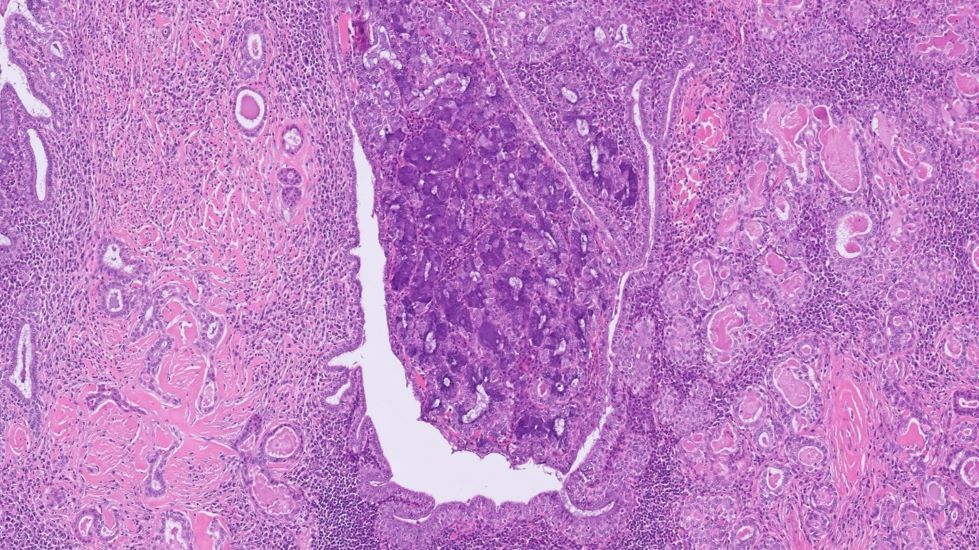

Mass in the maxillary sinus. Diagnosis: sinonasal ____ A) teratocarcinosarcoma B) SWI/SNF complex-deficient carcinoma C) germ cell tumor D) undifferentiated carcinoma 🔬tumourclassification.iarc.who.int/Viewer/Index2?… #BSTPath #HNPath #ENTPath #PathTwitter #Pathology

Mass in the maxillary sinus.

Diagnosis: sinonasal ____

A) teratocarcinosarcoma

B) SWI/SNF complex-deficient carcinoma

C) germ cell tumor

D) undifferentiated carcinoma

🔬tumourclassification.iarc.who.int/Viewer/Index2?…

#BSTPath #HNPath #ENTPath #PathTwitter #Pathology